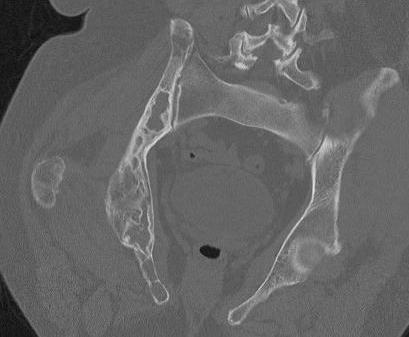

Spine involvement / scoliosis

- 62 patients with polyostotic FD

- 40% had scoliosis

Berglund et al J Bone Mineral Res 2018

- 138 patients with fibrous dysplasia / McCune Albright syndrome

- 61% scoliosis

- 35% moderate to severe

- no effect of bisphosphonates in reducing curve progression

CT